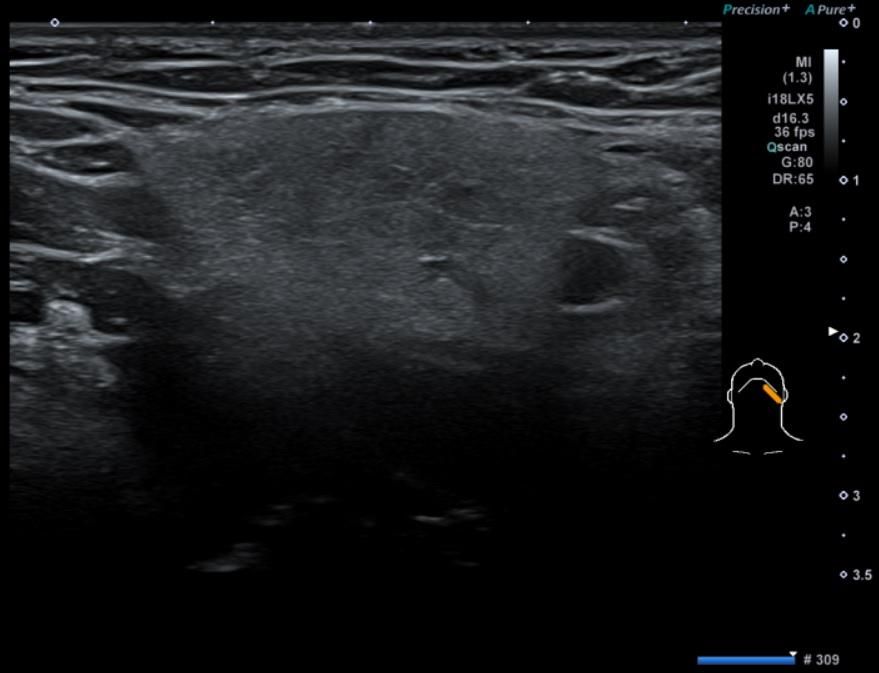

• 3번 째 사진